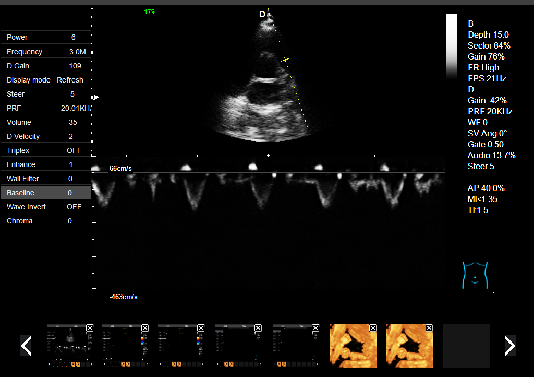

P5-VET手提式獸用彩超機心臟超聲檢查圖

心臟超聲檢查:

心臟超聲是唯一能動態顯示心腔內結構、心臟的搏動和血液流動的儀器,對人體沒有任何損傷。心臟的各個結構清晰地顯示在屏幕上。通過彩超的測量,醫生可了解瓣膜病變的程度以決定保守治療還是手術治療。心肌的增厚、心腔的擴大都要依賴彩超來判斷;對冠心病,彩超能直觀顯示心肌的運動狀況及心功能,向臨床醫生提示心肌缺血的部位。